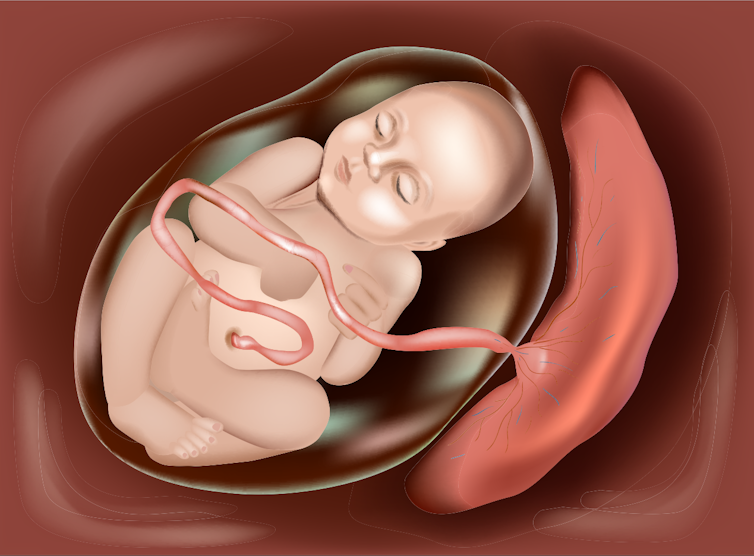

The embryo makes its way to the uterus, where it will grow for the next nine months, until the baby is ready to be born.

After the egg and sperm join to make an embryo, the embryo attaches to the mother’s uterus.

An organ called the placenta forms to supply the growing baby with all the nutrition it needs.

When the baby is ready to be born, the muscles of the mum’s uterus start to contract and push the baby out through the vagina.